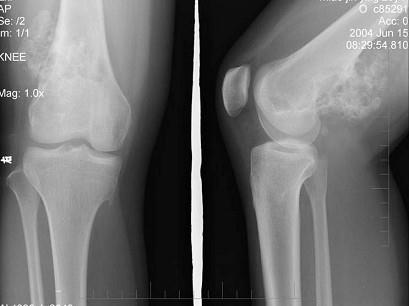

问题 女,20岁,右大腿远端疼痛2年,伴有肿块,请结合所提供图像,选择最佳答案 ( )

选项 A、纤维肉瘤 B、骨巨细胞瘤 C、软骨肉瘤 D、骨肉瘤 E、软骨黏液纤维瘤

答案 C